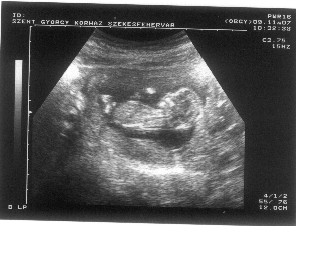

Tök jó képet kaptál róla, simán felismerhrtő minden! Bár Vegerától nem vártam sokat, nekem nem szimpi, mert ő paráztatott be a 7. héten, hogy nem él a baba...

Ha arra gyanakszik, hogy több hetes, igazán mondhatta volna, mennyinek gonolja, mi alapján, stb...de lényeg, hogy semmi baja! Mennyiért vettél övterelőt? Ja a mellső fali tapadásnak örülj, az a jó!